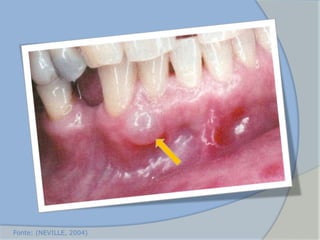

 Tumefação mole na mucosa gengival recobrindo a coroa de um

dente decíduo ou permanente em erupção

 Comum em crianças com menos de 10 anos de idade (1°s MP e IS)

 Quando são retirados intactos não são enviados para o histológico.

 Tratamento – simples excisão da corbetura do cisto.

2. Cisto de erupção

(NEVILLE, 2004)